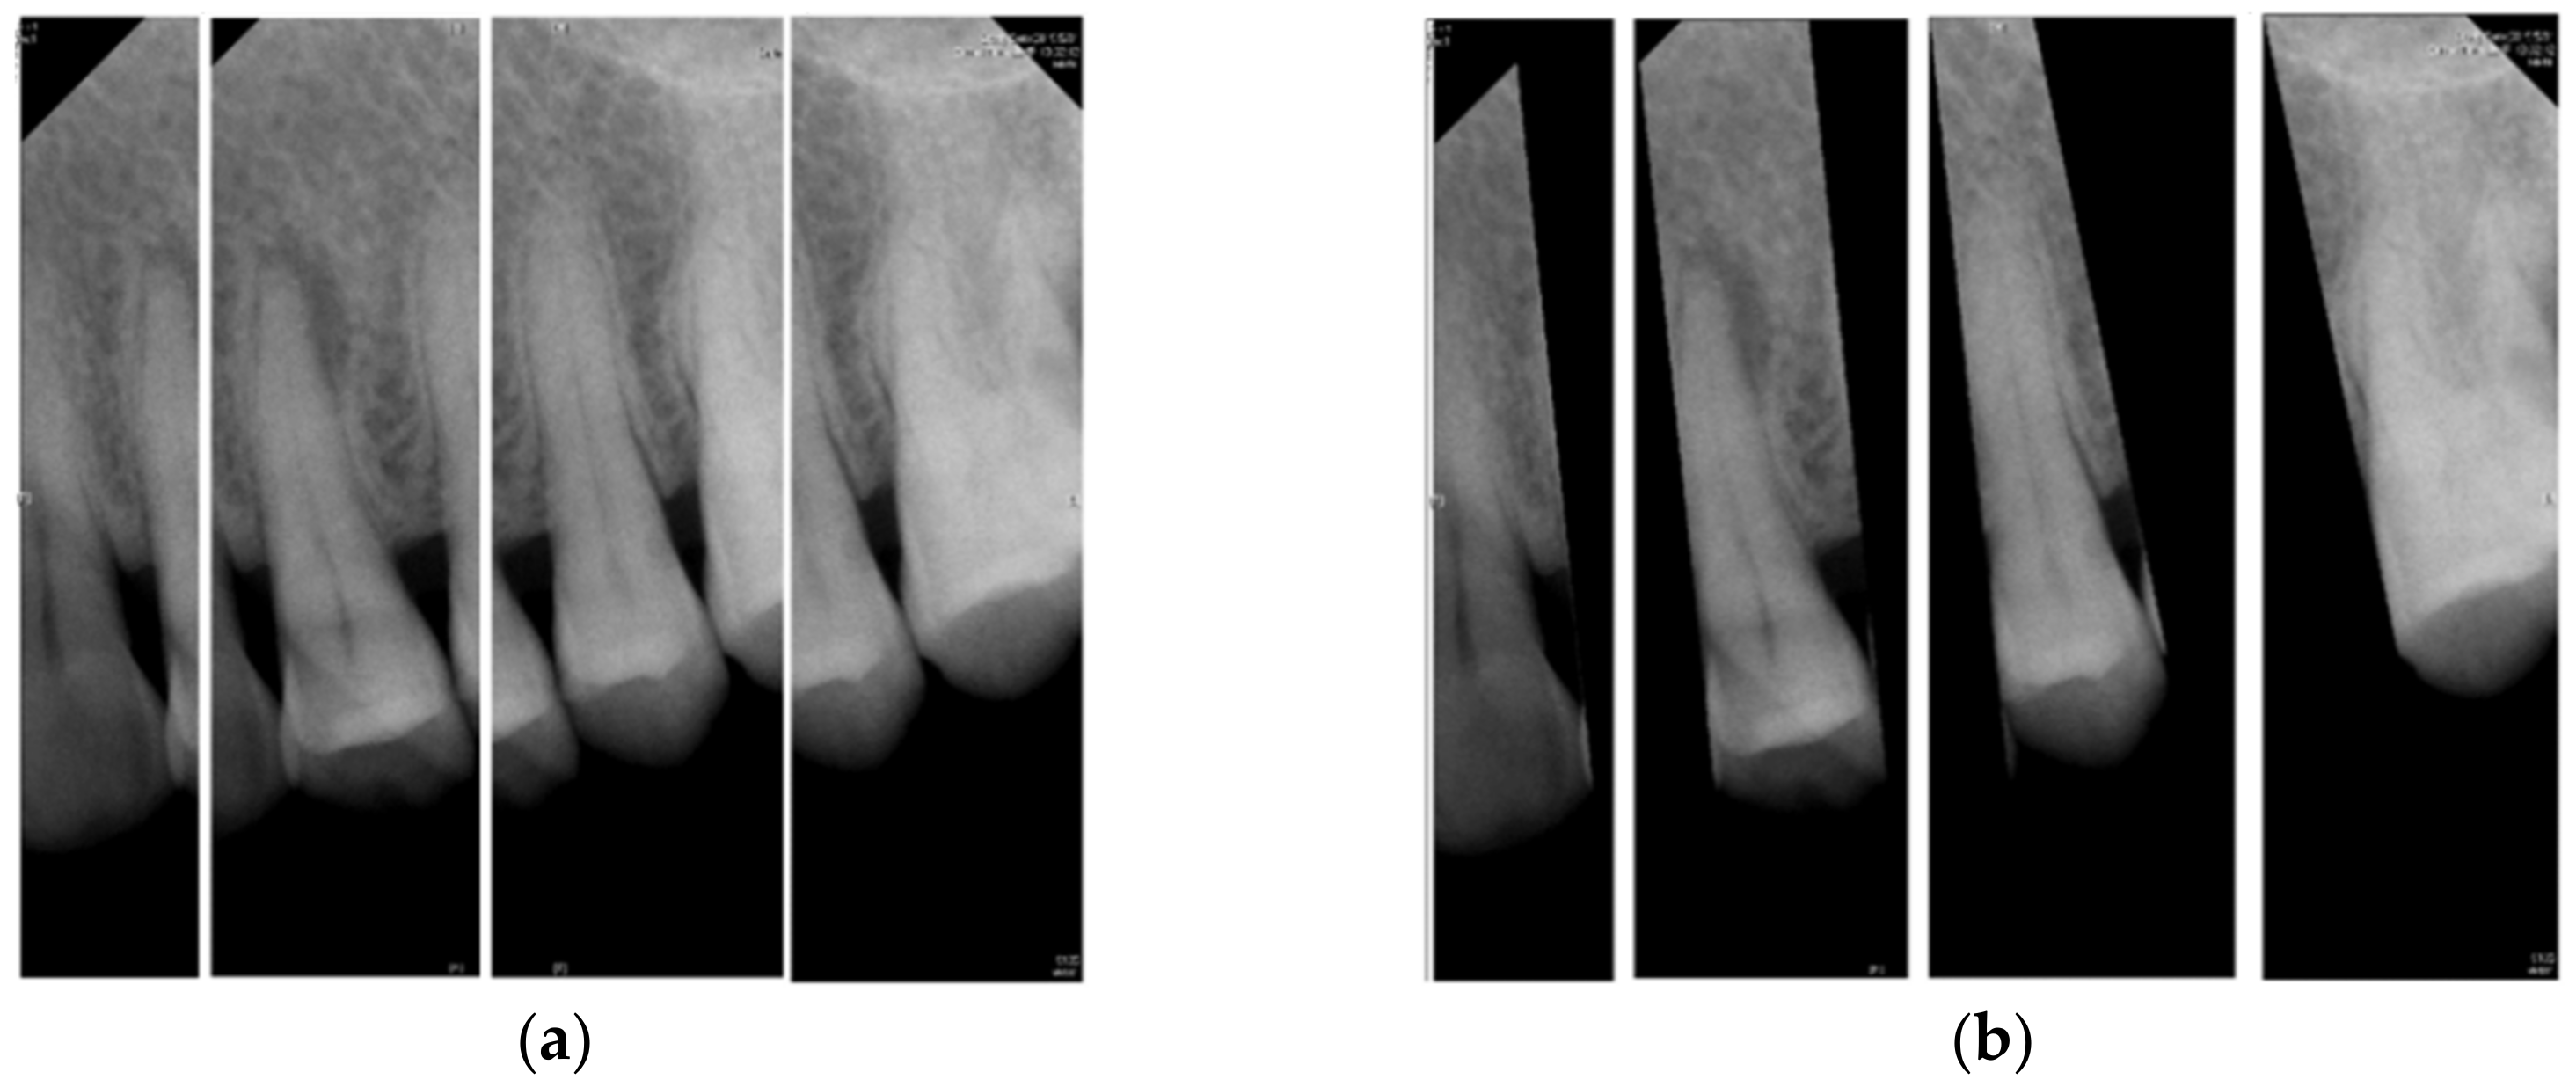

2.1.1. Vertical Cutting